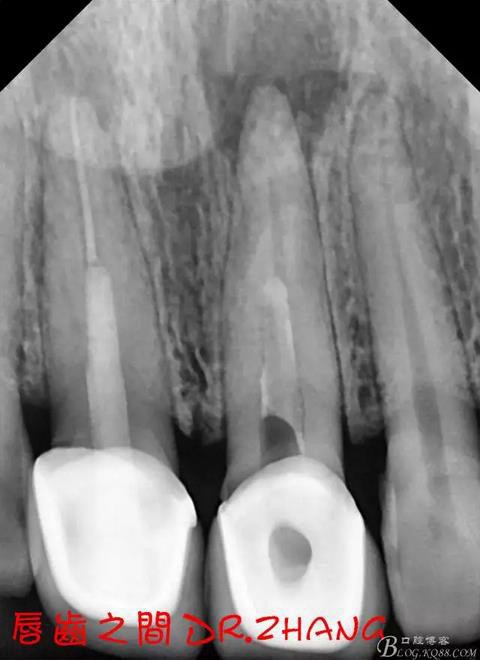

復(fù)診:腫脹明顯消失 患者自訴感覺良好 溝通后決定拆除11 21兩顆烤瓷冠后重新修復(fù) 去冠器直接去冠 去除11根管內(nèi)的充填物 15#K銼疏通根管 11 21根長均為16MM平斷面 薩尼S3系統(tǒng)機擴至2S 期間不斷用氯己定和鹽水交替沖洗 吸潮紙尖干燥根管后06 25#試尖

思博安熱牙膠系統(tǒng)根充 燙斷至根尖三分之一處后纖維樁恢復(fù)牙體組織